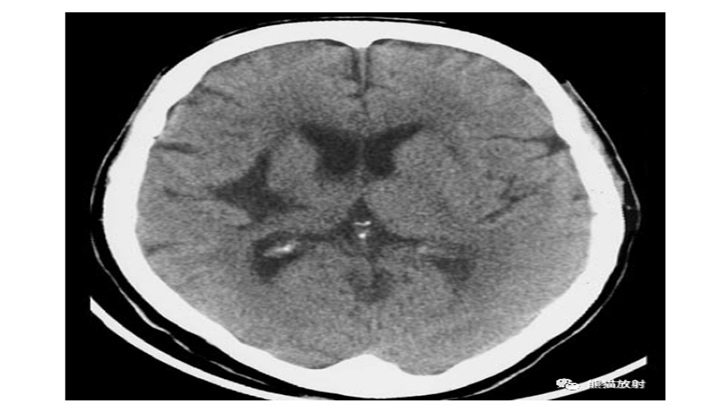

丘脑血肿,范围有限,保守治疗即可。对侧顶叶低密度楔形病变,陈旧性脑梗死。血肿占位效应明显(第三脑室变形)和脑室内积血,具有致命的后果。